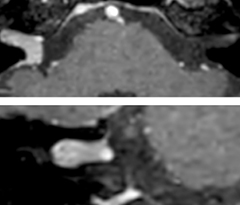

This is an example of acute ischemic stroke with distal occlusion of the right posterior cerebral artery. Note the improved visibility of the ischemic territory on the diffusion weighted image with high b-value. The 3D FLAIR shows a distal PCA occlusion. The fast SWIp depicts the thrombus on the isolated second echo image. The total scan time (including SmartBrain, preparations and a fast 3D T1w TSE Gd) is 8:00 minutes.